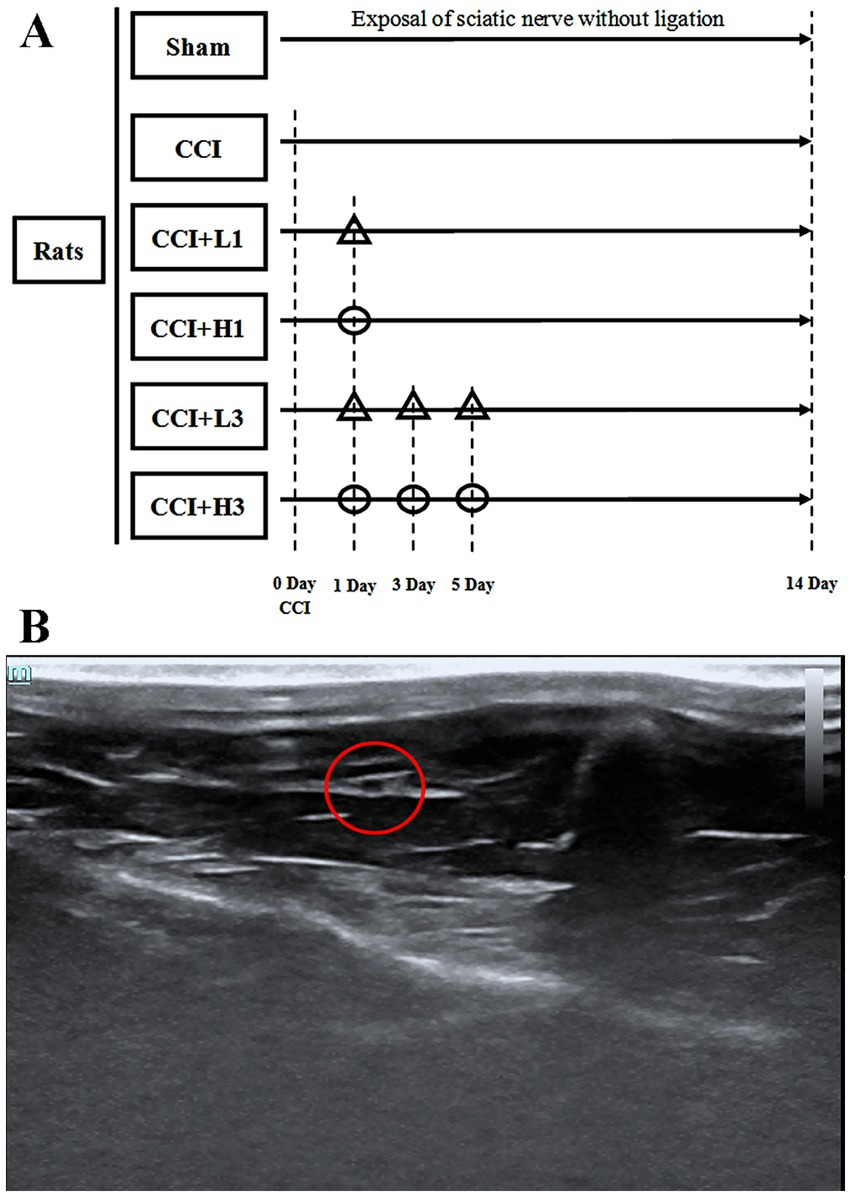

慢性压迫性损伤模型构建完成后,将36只大鼠随机分为以下6组(每组6只):

1. 假手术组:仅暴露左侧坐骨神经,不进行结扎;

2. 模型组:仅构建慢性压迫性损伤模型,不给予其他干预;

3. 低浓度纳米气泡溶氢水单次注射组(CCI+L1组):慢性压迫性损伤造模后第1天,超声引导下局部注射低浓度纳米气泡溶氢水(浓度1300 ppb,剂量5毫升/千克);

4. 高浓度纳米气泡溶氢水单次注射组(CCI+H1组):慢性压迫性损伤造模后第1天,超声引导下局部注射高浓度纳米气泡溶氢水(浓度2600 ppb,剂量5毫升/千克);

5. 低浓度纳米气泡溶氢水三次注射组(CCI+L3组):慢性压迫性损伤造模后第1、3、5天,超声引导下分三次局部注射低浓度纳米气泡溶氢水(浓度1300 ppb,剂量5毫升/千克);

6. 高浓度纳米气泡溶氢水三次注射组(CCI+H3组):慢性压迫性损伤造模后第1、3、5天,超声引导下分三次局部注射高浓度纳米气泡溶氢水(浓度2600 ppb,剂量5毫升/千克)。

(见图1A)

图1 (A)研究方案设计。CCI:慢性压迫性损伤;△:超声引导下坐骨神经局部注射低浓度纳米气泡溶氢水(1300亿分比浓度);○:超声引导下坐骨神经局部注射高浓度纳米气泡溶氢水(2600亿分比浓度)。(B)超声下的坐骨神经影像。红色圆圈标记处为坐骨神经。

参照既往研究方法(Wu 等, 2023)开展超声引导下局部注射操作。大鼠吸入2%异氟醚麻醉后,使用超声成像仪(深圳迈瑞生物医疗电子股份有限公司)搭配高频探头(带宽15~30兆赫兹),对大鼠左后肢腹侧区域进行超声扫描(见图1B)。穿刺操作前,需清理观察区域毛发,并采用碘伏进行局部消毒。